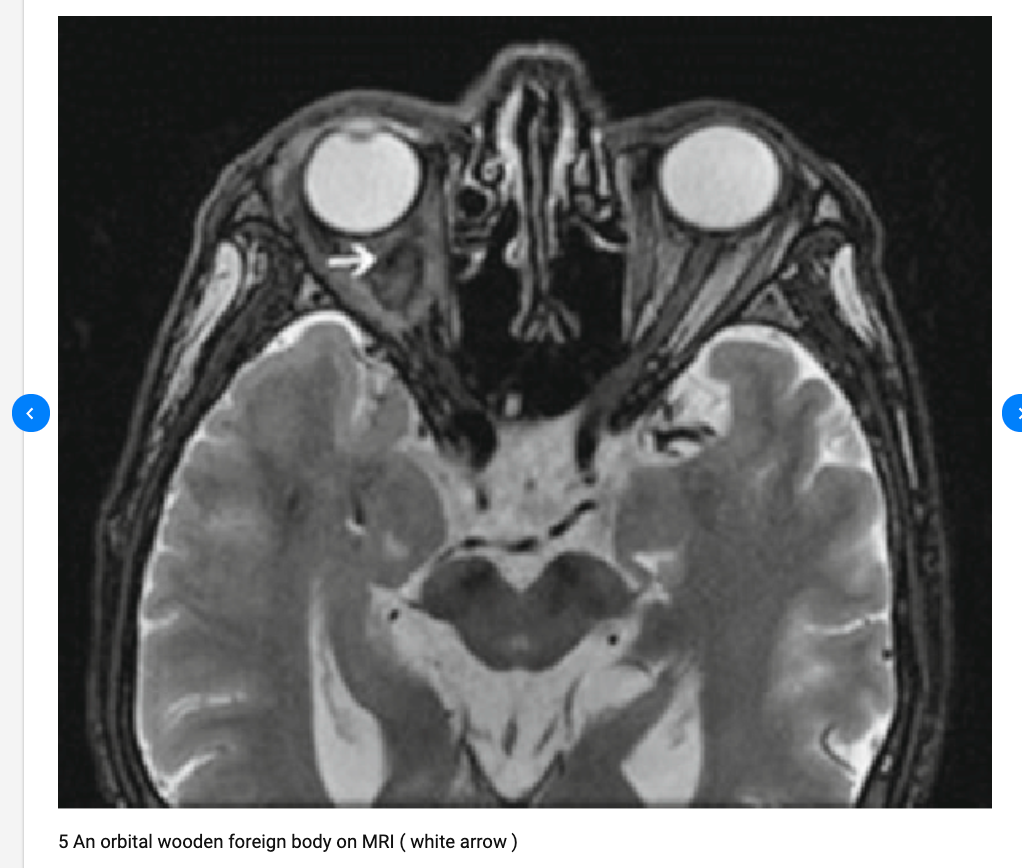

Detection of Occular FB

Wood